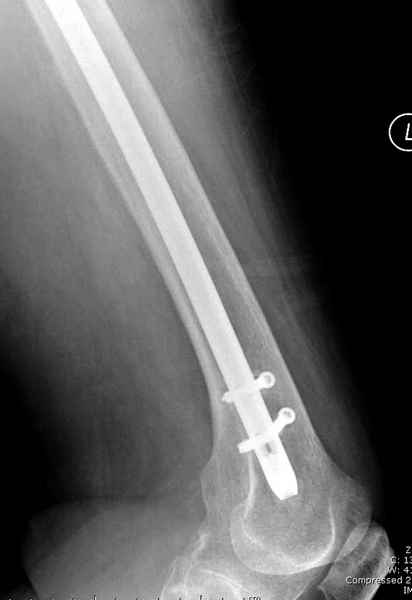

77 летняя больная направлена в нашу клинику на дальнейшее лечение. Из истории, травму получила в сентябре 2007 года и по поводу перелома шейки бедра больная была проперирована тремя каннюлированными шурупами с явным нарушением технологии установки шурупов. Внизу вместо одного шурупа имеется два, что привело к стрессу латерального кортекса. Через месяц по поводу ятрогенного подвертельного перелома сделана фиксация длинной Гамма 3. Установлен без проксимальной блокировки? (set screw). В данный момент имеется несостоятельность конструкции и ложный сустав. Передвигается с помошью костылей, конечность укорочена на 2 см. Какие будут рекомендации?Djoldas Kuldjanov, MDDepartment of Orthopedic SurgerySt. Louis University Medical Center

Михаил, здравствуйте. Если присмотреться - на четвертом снимке есть перелом гвоздя по отверстию.

Видимо, проблем тут две: во-1-х, центральный отломок был оставлен в варусно-сгибательной установке, во-2-х, не динамизировали вовремя.

Нижние винты хотели сломаться, но, увы, один не сломался, и тогда сломался гвоздь. Хотя и при динамизации в таком положении отломков

могло не срастись.